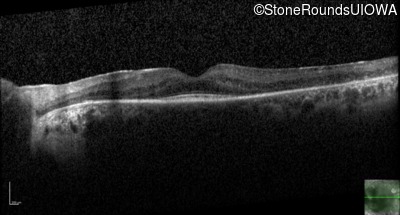

Optical Coherence Tomography - Right - 20/40

Exemplar / OCT Stack

OCT Stack